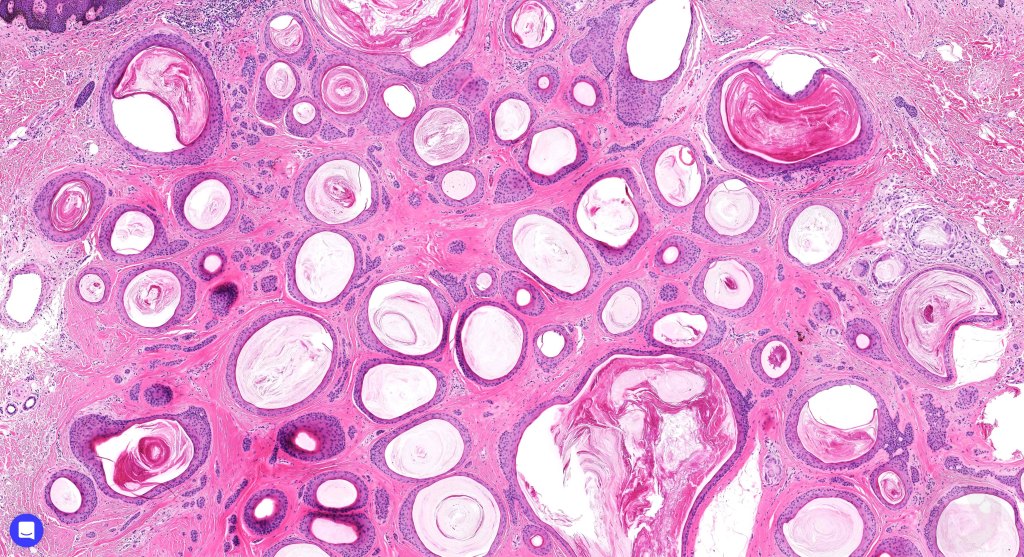

Histological features

•Keratocysts showing infundibular keratinization i.e.with a granular cell layer

•Solid epithelial islands

•Fibrovascular stroma